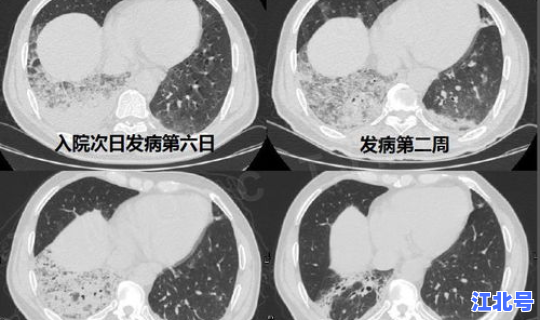

患者主要临床表现为发热 、乏力,呼吸道症状以干咳为主 ,并逐渐出现呼吸困难,严重者表现为急性呼吸窘迫综合征、脓毒症休克、难以纠正的代谢性酸中毒和出凝血功能障碍 。部分患者起病症状轻微,可无发热。

多数患者为中轻症 ,预后良好,少数患者病情危重,甚至死亡。